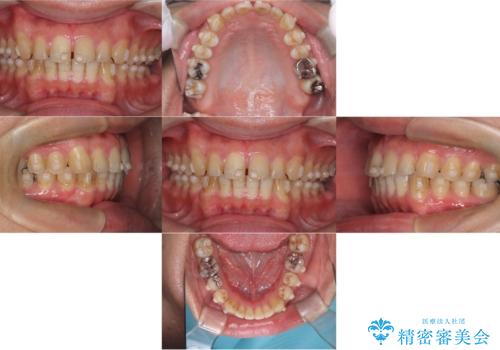

- 前歯の隙間と歯のデコボコを主訴にご来院された患者様です。

加えて、上下の奥歯が全く咬み合わないシザーズバイトの状態も認められました。

矯正検査の結果、非抜歯でインビザラインによる治療が可能と判断し、治療を行いました。

歯の隙間とデコボコ、シザーズバイトも改善され、咬み合わせや見た目が整い、患者様にも大変ご満足いただけました。